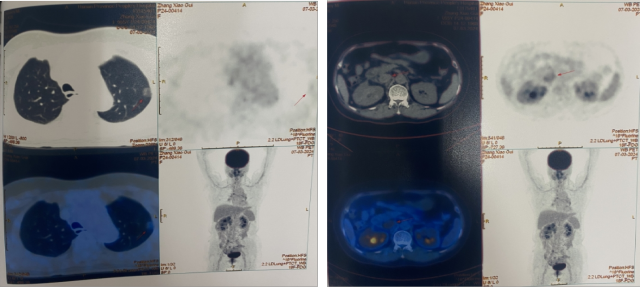

PETCT(2022.10):1. 左侧肾上腺结节灶,糖代谢增高,转移瘤可能性大;2. 左肾多发结节状突起,糖代谢增高,考虑转移瘤,需结合增强 CT 综合判断;3. 右下肺切除术后,术区未见复发;4. 右侧胸壁局部增厚、糖代谢增高,术后改变?建议追踪。

靶免联合治疗 1 年后复查

CT(2023.7.17):1. 左肾上腺结节、左肾结节及肿块较前明显增大:转移?左肾 CA 并左肾内、肾上腺转移?2. 腹膜后淋巴结较前增大,转移可能;3. 余况基本同前。